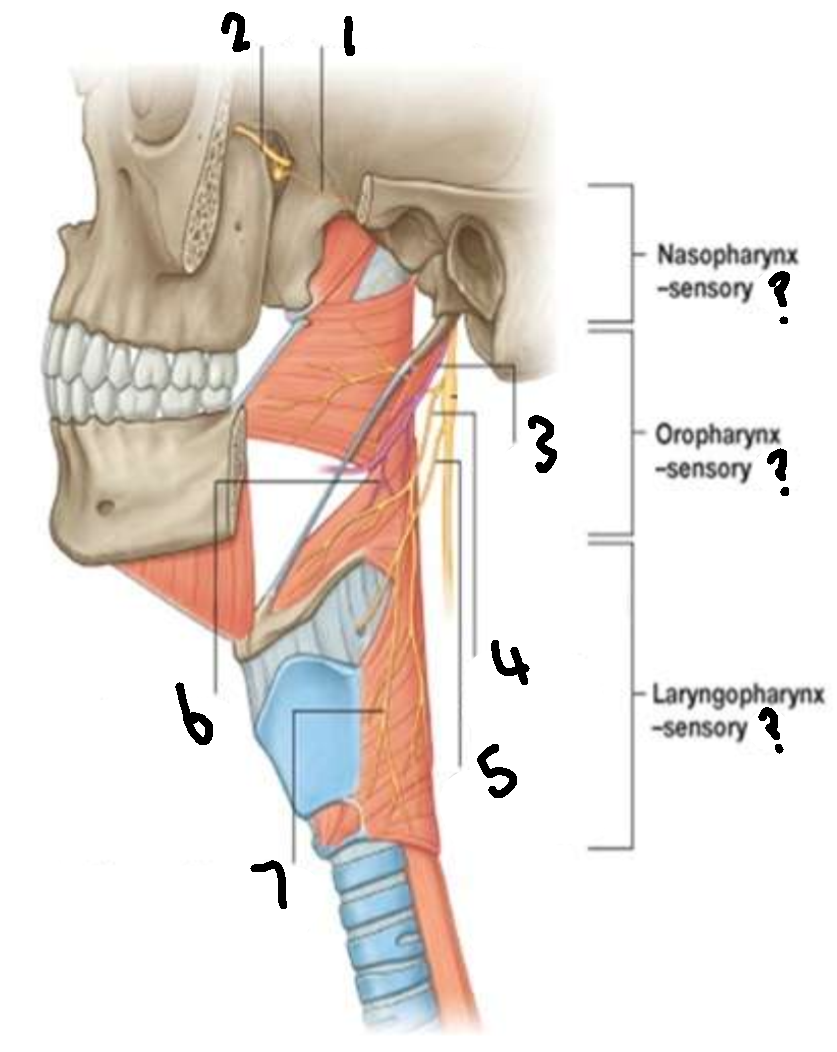

What provides sensory innervation to the nasopharynx?

mandibular branch of trigeminal V2

What provides sensory innervation to the oropharynx?

glossopharyngeal IX

What provides sensory innervation to the laryngopharynx?

vagus X

What is 1?

pharyngeal branch of V2

What is 2?

maxillary branch of trigeminal V2

What is 3?

glossopharyngeal IX

What is 4?

pharyngeal branch of vagus X

What is 5?

superior laryngeal nerve

What is 6?

pharyngeal branch of IX

What is 7?

external laryngeal branch of superior laryngeal nerve of X